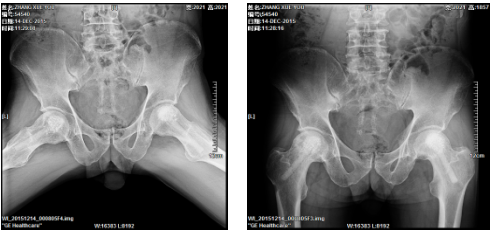

2、髋关节全髋、半髋置换手术、膝关节表面置换手术、关节融合手术。

1、在医院领导的大力支持下,和上海贝奥路生物材料学有限责任公司卢建熙教授(法国医学科学家、上海市六院骨科教授)合作,成功在全省率先开展陶瓷棒微创技术治疗股骨头无菌性坏死的创新技术得到了市科技局和社会的认可。